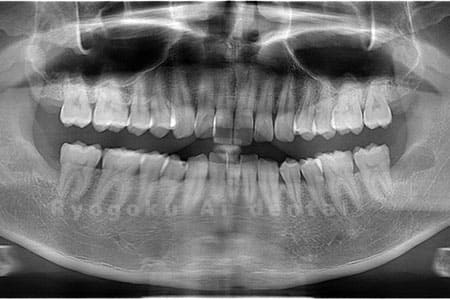

Case04

- 原因

- 上顎の親知らず、下顎の水平埋伏の親知らず

- 治療内容

- 上顎の親知らず、下顎の水平埋伏の親知らずを抜歯したケースです。

<リスク・副作用>

手術後は痛み、腫れ、痺れなどの副作用が生じる場合があります。